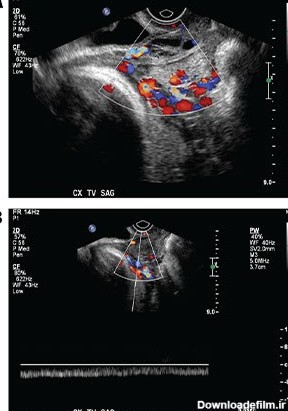

برای بررسی علت تأخیر باروری، باید سلامت اندامهای تولید مثل مورد ارزیابی قرار گیرند؛ یکی از روشهای تشخیصی که برای بررسی رحم و لولههای رحمی درخواست می شود، هیستروگرافی است. با این تست، پزشک از وضعیت داخلی رحم و لوله های رحمی مطلع میگردد و با توجه به نتایج حاصل از تست، در مورد نحوه درمان تصمیم خواهد گرفت. انجام این تست در ارزیابی ناباروری بسیار مهم است.

مرکز سونوگرافی الوند با حضور کادر مجرب و آموزش دیده و با استفاده از بروزترین تجهیزات روز دنیا خدمات سونوگرافی مانند سونوگرافی بارداری، سونوگرافی غدد لنفاوی، سونوگرافی هیستروگرافی، سونوگرافی مپینگ اندومتریوز، خدمات ماموگرافی دیجیتال، فیبرواسکن یا الاستوگرافی ارائه می دهد.